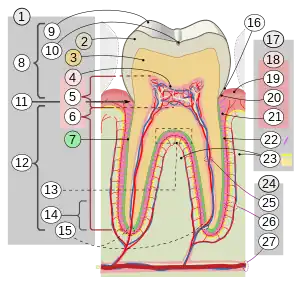

2. Enamel

3. Dentin

4. Dental pulp

5. cameral pulp

6. root pulp

7. Cementum

8. Crown

9. Cusp

10. Sulcus

11. Neck

12. Root

13. Furcation

14. Root apex

15. Apical foramen

16. Gingival sulcus

17. Periodontium

18. Gingiva

19. free or interdental

20. marginal

21. alveolar

22. Periodontal ligament

23. Alveolar bone

24. Vessels and nerves

25. dental

26. periodontal

27. alveolar through channel